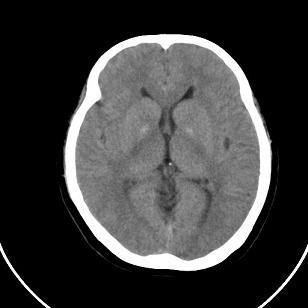

双侧脑室边缘呈波浪样,没有见过?

小脑后的囊状低密度影,里面可见分隔,考虑枕大池还是蛛网膜囊肿。

双侧脑室外缘灰质密度结节应该是尾状核的体部;枕大池前缘受压前移位,考虑囊肿

不知患者有无临床症状,双侧侧脑室边缘不规则,呈波浪状,考虑脑室周围白质软化症可能性大

这个病例不符合脑室周围白质软化症

是不是应该考虑结节性硬化或者灰质移位,建议mri

支持灰质移位,mri检查有必要.枕大池蛛网膜囊肿.

1)脑灰质异位。2)双侧枕部颅骨内板下方类似扇形及弧形脑脊样低密度影;鉴别于巨大枕大池与蛛网膜囊肿之间。建议必要时行进一步检查。